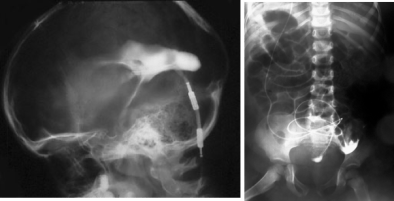

le protocole détaillé ci-dessous nécessite une hospitalisation avec test d’opacification au bloc opératoire (l’opacification radiologique nécessite d’avoir implanté au départ une valve avec réservoir) ; c’est la dernière survivance de la ventriculographie (Cf. ci-contre).